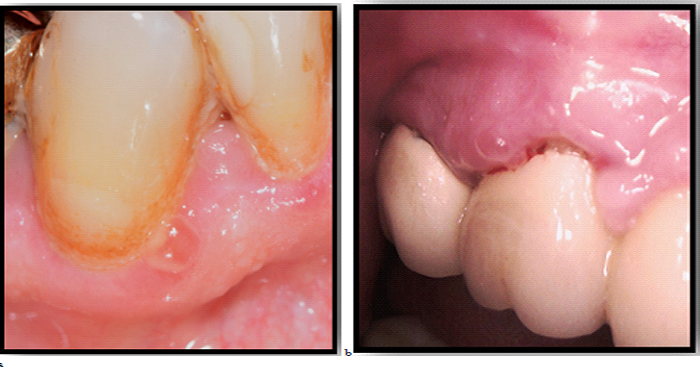

During the scheduled visit to dental office a 54-year-old male was diagnosed with bullae in vestibular aspect of right maxilla. He was reported to the outpatient Department of Oral and Maxillofacial surgery, FDM, MU - Sofia, with a chief complaint of bullae. He has no history of difficulty in swallowing food or any eyesight problems. On general physical examination there were not any complaints and findings. On intraoral examination, a solitary intact bullae measuring about 5 mm in diameter was present on the upper labial mucosa.(Fig.1.) No other bullae and vesicles were founded. Based on patient's history and clinical presentation, a provisional diagnosis of mucous membrane pemphigoid was considered. After the rupture of bullae it left large, superficial, ulcerated, and denuded areas of mucosa.

Figure-1.The initial detected lesion

Source: Photo is taken by us- clinical case, that we describe

Figure-2. Bullous lesions of oral mucosa- a,b

After some days others lesions were presented in oral mucosa-Fig.2-a,b, fig.3